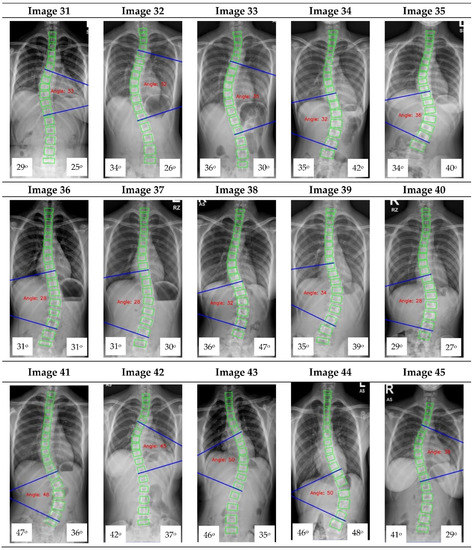

The Cobb angle measurement of the scoliotic spine is prone to inter- and intra-observer variations in the clinical setting. This paper proposes a deep learning architecture for detecting spine vertebrae from X-ray images to evaluate the Cobb angle automatically. The public AASCE MICCAI 2019 anterior-posterior X-ray image dataset and local images were used to train and test the proposed convolutional neural network architecture. Sixty-eight landmark features of the spine were detected from the input image to obtain seventeen vertebrae on the spine. The vertebrae locations obtained were processed to automatically measure the Cobb angle. The proposed method can measure the Cobb angle with accuracies up to 93.6% and has excellent reliability compared to clinicians’ measurement (intraclass correlation coefficient > 0.95). The proposed deep learning architecture may be used as a tool to augment Cobb angle measurement in X-ray images of patients with adolescent idiopathic scoliosis in a real-world clinical setting. Full article

Show Figures

Figure 1